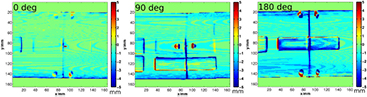

Standard image High-resolution imageFigure 8 presents the WET evaluation at 0°, 90° and 180° and mid-depth when the vCTCBCT and refCTCBCT are compared. The results of the WET evaluation are summarized in table 5. For the ΔWET evaluation of table 5 the rows of pixels where the beam was tangential to the phantom surface (2 pixel rows on either side of the phantom) were excluded from the analysis as the very low WET values gave relative WET differences larger than 100%. Additionally, pixels with WET differences larger than 40 mm were considered outliers. For the gamma evaluation all pixels were considered. We observed that few pixels pass the gamma evaluation and that the average WET difference was large when comparing the pCTCBCT and the refCTCBCT, as can be expected from the removal of the outer ring, which is 7 mm thick. Comparing the vCTCBCT and refCTCBCT yielded a high level of passing pixels (> 98%) and mean WET differences of the order of −1 mm at the center of the phantom and −2 mm when traversing the whole phantom. These differences correspond to about −2 to −2.5% of the WET. Most of the WET differences were observed at the border of the phantom as seen in figure 8. This is caused by an imperfect correction of the phantom diameter following the removal of the outer ring. Such an effect is visible in in the vCT versus refCT comparison of figure 3(f) at the right and bottom edges of the phantom. The slight mismatch is sufficient to cause large WET differences at edges; however these WET errors would not appear in dose distributions for beams covering the central part of the phantom. In that case the error would be limited to the mismatch of phantom diameter, which is of the order of 1 mm.

Figure 8. WET difference maps in mm between the vCTCBCT and refCTCBCT (WETvCT–WETrefCT) at 0°, 90° and 180° and mid phantom depth.

Standard image High-resolution imageWe observed that the WET evaluation was not particularly sensitive to the smaller changes of configurations 1 and 2 as opposed to configuration 3. The vCTCBCT results were consistent across configurations.

3.3. Dosimetric evaluation

Figure 9 presents the range difference maps corresponding to the 0°, 90° and 180° beams. We observe that range differences are reduced when using the vCTpCT instead of the pCTpCT. Since range is calculated from the phantom surface, the 7 mm difference caused by the weight loss ring removal does not show in the pCTpCT versus refCTpCT comparison. Larger deviations are observed for the pCTpCT versus refCTpCT at 180° due to the different airway diameter. Generally the range differenced between the vCTpCT and refCTpCT are of the order of 2 mm or less.

Figure 9. BEV range differences between (left) the vCTpCT and refCTpCT (rangevCT–rangerefCT) and (right) the pCTpCT and refCTpCT (rangepCT–rangerefCT) at 0°, 90° and 180°. Range was calculated from the phantom surface to the 80% distal falloff.